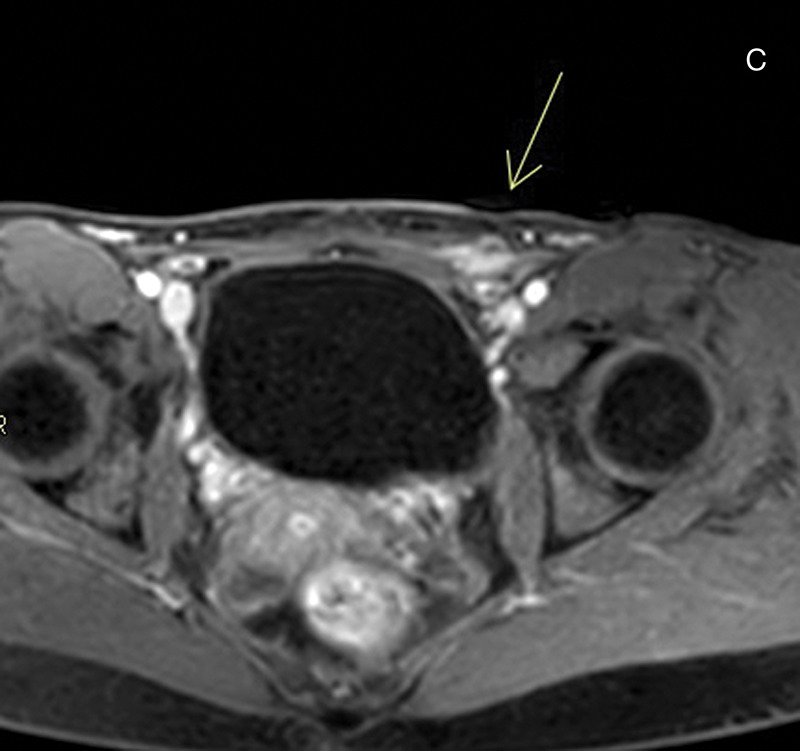

教学要点:磁共振成像(MRI)在诊断子宫内膜异位症中的作用越来越大,要求放射科医生熟悉深浸润性子宫内膜异位症的典型和非典型表现。

Teaching point: The role of magnetic resonance imaging (MRI) in diagnosing endometriosis is growing, requiring radiologists to become familiar with both typical and atypical presentations of deep infiltrating endometriosis.